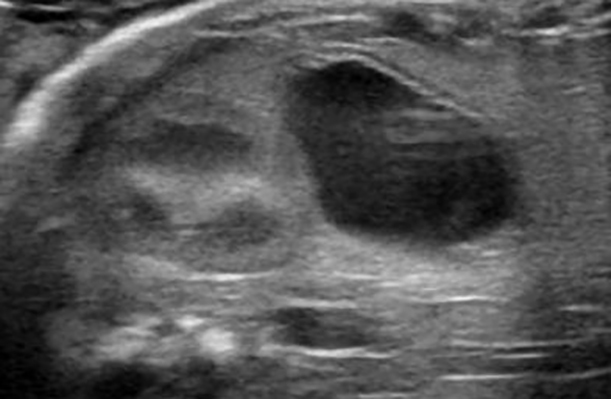

発情期の卵巣

卵胞から黄体への移行

卵胞(5mm 黒い丸)が排卵後、黄体(中が白くなります)へ移行。